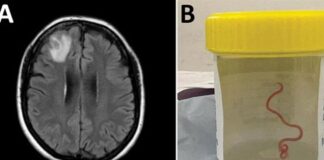

خانه برچسبها مغز انسان، کرم انگلی

Tag: مغز انسان، کرم انگلی